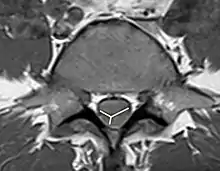

As the non-contrast CT and spine CT angiography are ineffective in imaging modalities, doctors use MRI to confirm the diagnosis. MRI findings, including pencillike hyperintensities on T2-weighted sagittal images and “owl’s eyes” or “snake eyes” sign on T2 axial images, indicate the infarction is predominately in the watershed area of the gray matter of ventral horn (anterior spinal artery infarct).[10] Also, posterior paramedian triangular hyperintensity in T2 hyperintensity indicates posterior spinal artery infarct. On a T1 sequence, we may also observe a cord expansion and a decreased signal.[18] However, traditional MRI may show no abnormality especially for those patients in the acute phase.[8] DWI is very sensitive for early detection of spinal cord infarction and shows a typical high signal intensity.[19]

To identify the hematoma in the spinal cord, MRI with and without gadolinium enhancement is the preferred choice.[9] CT is also used to identify the hemorrhage and provide evidence for pathological analysis. Complete spinal MRI with MR angiography is used when patients with subarachnoid hemorrhage without the intracranial etiology.[20] As the evaluation of the need for intradural interrogation is important, it is necessary to differentiate between subdural and epidural hematomas. Based on the location of the hematoma, use both axial and sagittal images of MRI to identify the boundary between hematoma and fat.[7] An inverted Mercedes-Benz sign shows the spinal subdural hematoma on the axial image.[21]